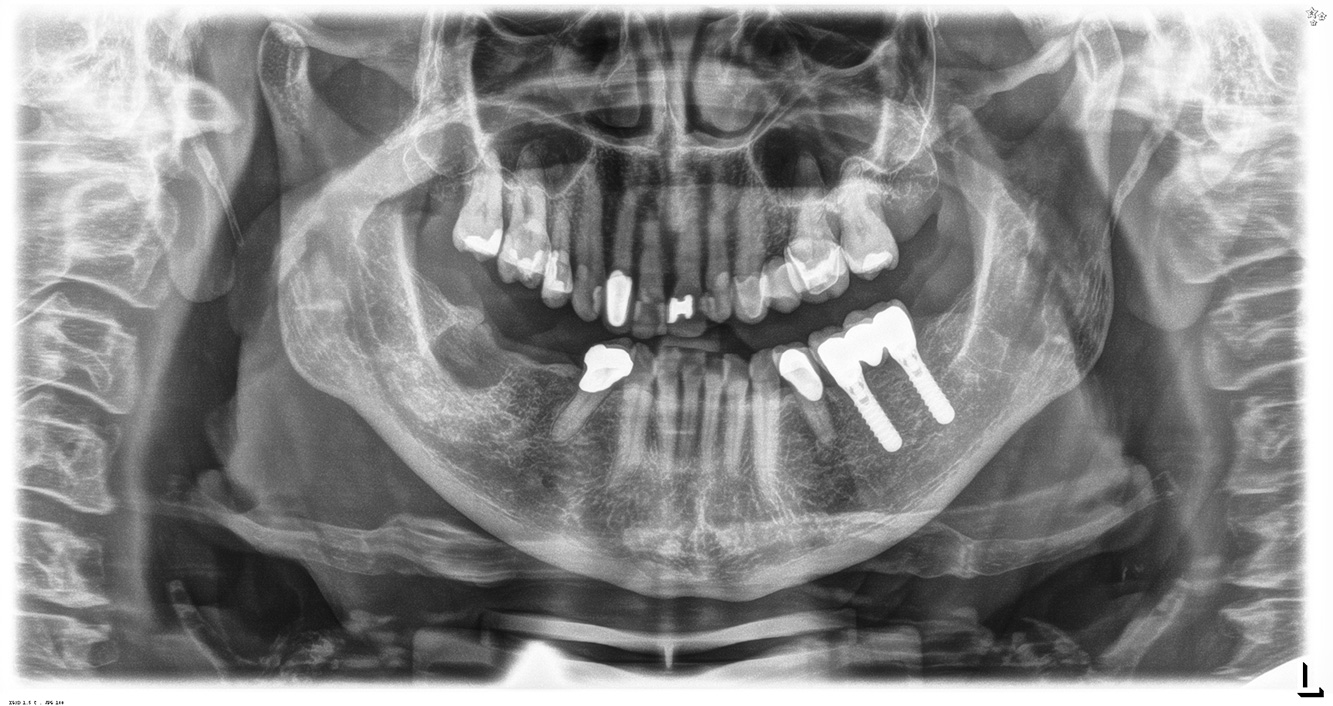

Questa paziente di 68 anni non presenta alcuna patologia precedente né segue alcuna terapia che possano ritenersi rilevanti dal punto di vista odontoiatrico, e il suo stile di vita non comporta alcun rischio particolare. La paziente ha due impianti (3° quadrante, da cinque anni) e una precedente patologia parodontale (parodontite allo stadio IV, grado B) con perdita del dente. Al momento le condizioni parodontali sono stabili, tuttavia la parodontite aumenta in misura significativa le complicazioni biologiche degli impianti e c'è dunque il rischio di perdita dell'impianto (21). Per la seduta di profilassi si possono formulare quattro consigli.